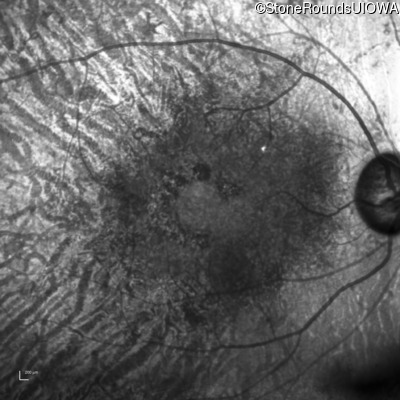

AR Retinitis Pigmentosa (IA1aiii)

Age at visit: 62 years

OD OS

This 62 year old man had poor night vision as a teenager and developed difficulty with his peripheral vision in his early forties. His parents both grew up in the small village in Taiwan.

Diagnosis & molecular findings

Disease Gene Allele 1 variant(s) Allele 2 variant(s) Inheritance mode

AR Retinitis Pigmentosa EYS Cys2139Tyr TGT>TAT Cys2139Tyr TGT>TAT AR